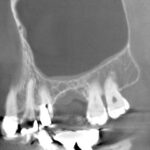

1ミリ以下の薄い骨でも大丈夫

ラテラルスリット法ではすべての骨の厚さに対応することができ、インプラント治療で大事な初期固定も十分確保することができます。骨が薄すぎてインプラント治療は無理ですといわれた方、大学病院での移植などを勧められた方。一度当歯科医院にご相談においでください。